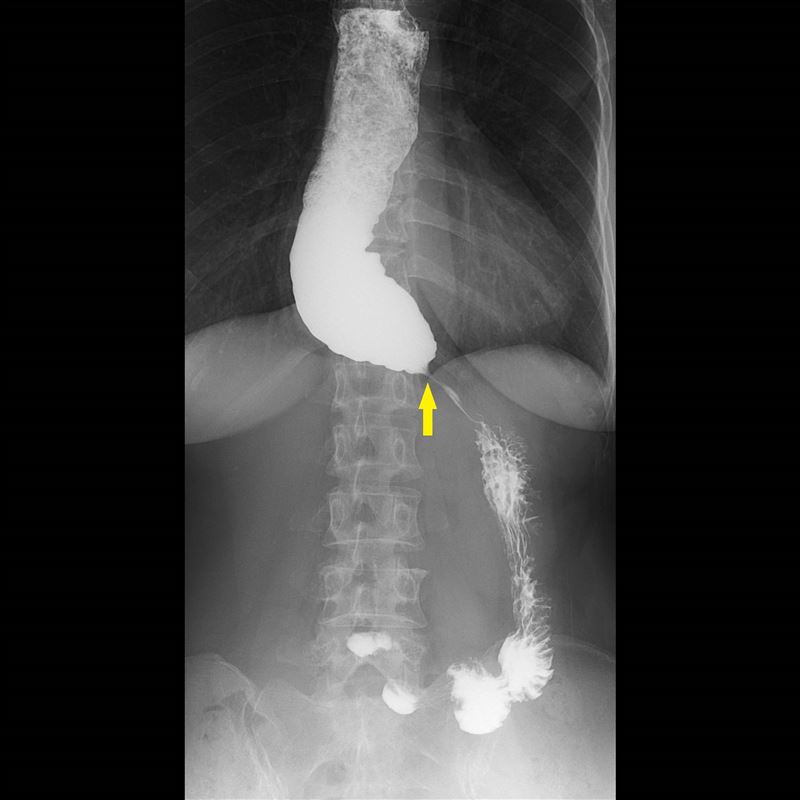

60歲蕭女士多年來飽受進食後胸口悶脹、食物卡在胸口的不適所苦,症狀持續數年卻始終未能明確診斷。輾轉來到台北慈濟醫院後,首先接受食道攝影與食道高解析度壓力檢測(HRM),其中食道攝影顯示食道末端出現典型「鳥嘴狀」狹窄,但壓力檢測結果卻沒有典型下食道括約肌壓力上升表現,讓診斷一度陷入兩難。後續接著以新式診斷工具功能性管腔成像探頭(Functional Lumen Imaging Probe, Endoflip)檢查,成功確診為「食道弛緩不能症」,讓患者順利進行後續治療。

台北慈濟醫院胃腸肝膽科醫師詹崴宇指出,食道弛緩不能症是一種食道神經肌肉功能障礙疾病,主要是神經退化致使食道壁內神經節細胞變性、減少,導致下食道括約肌持續緊閉,食物無法順利進入胃部的一種罕見疾病。台灣年平均發生率約為每十萬人1.64例,男女都有發生可能,易發生在年長者。常見症狀包括固體與液體皆有吞嚥困難、胸痛、胃酸逆流、飯後嘔吐及體重減輕等;若長期未接受治療,食道可能因食物堆積而嚴重擴張,形成不可逆的「巨大食道」,即使後續解除下端的出口梗阻,食道上方嚴重擴張卻已無法復原。